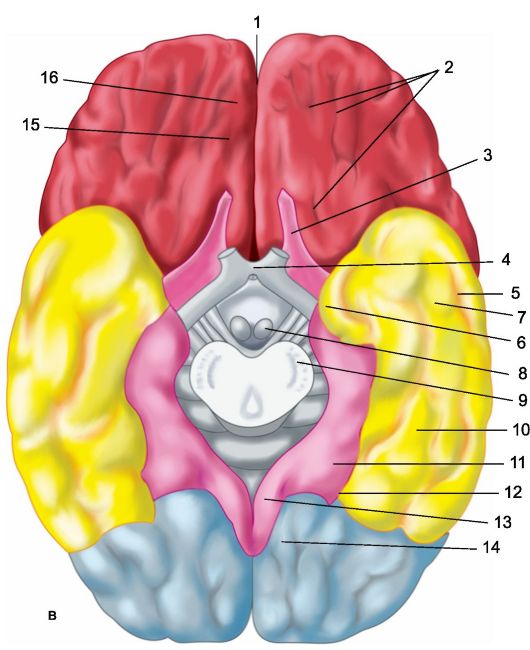

Анатомические снимки верхнелатеральной поверхности головного мозга